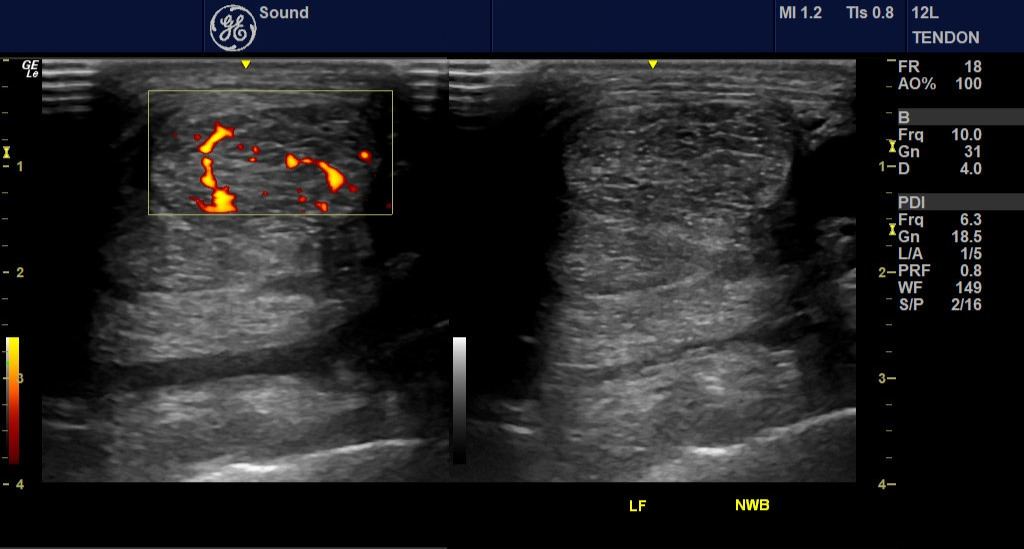

Doppler ultrasound adds a new dimension by assessing blood flow, helping us determine whether a lesion is active, inflamed, or in the healing phase. This difference matters when you’re treating high-level performance horses.

Doppler ultrasound—specifically color and power Doppler—allows us to evaluate blood flow within or around a lesion. Why is this helpful?

– Active lesions often show increased vascularity (neovascularization)

– Older, scarred injuries typically have little to no blood flow

Doppler helps us go beyond structure and assess activity and inflammation. This is especially helpful in chronic or recurring injuries, where clinical signs may not match the grayscale appearance.